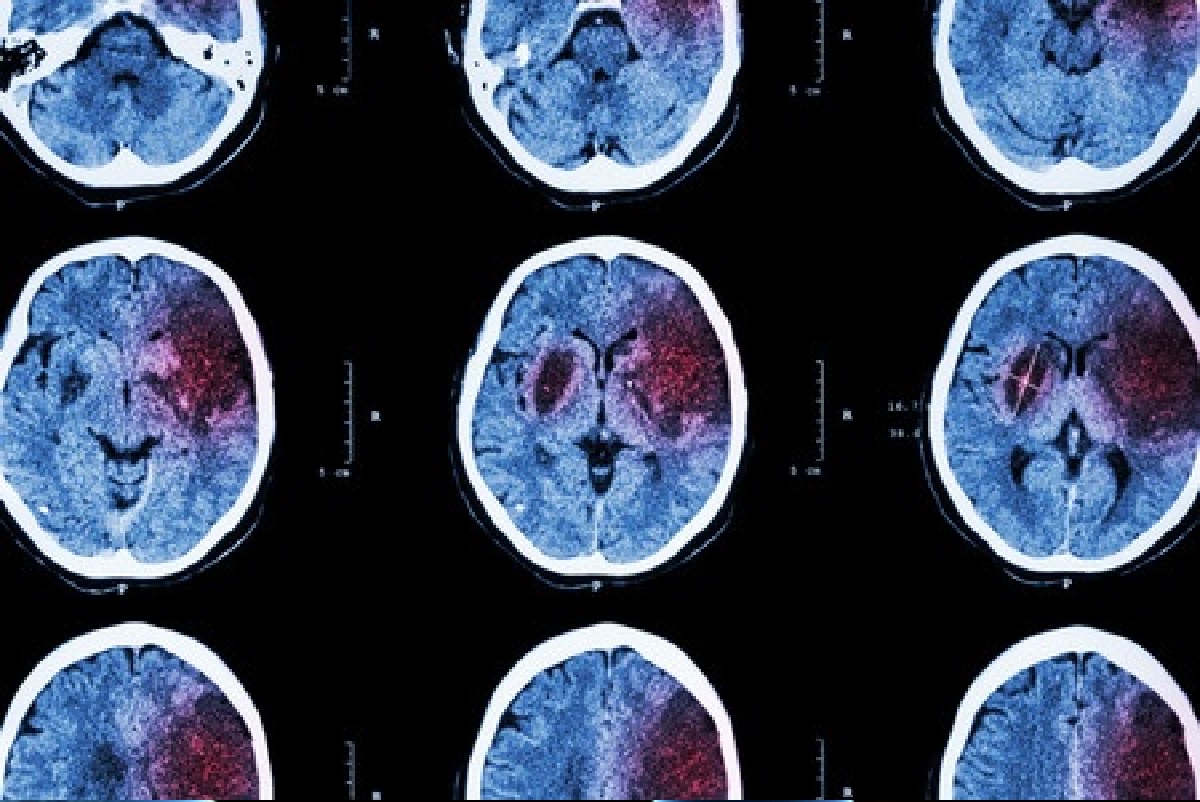

La cardiopatía isquémica es la primera causa de fallecimiento en el mundo, seguida de las enfermedades vasculares cerebrales. Estos datos convierten la enfermedad vascular en la principal causa de mortalidad a nivel mundial, y en la primera también de discapacidad adquirida en el adulto. Pero la buena noticia es que el 90 por ciento de sus factores de riesgo se pueden prevenir.

La Dra. Araceli García Torres, jefa asociada del Servicio de Neurología del hospital madrileño y coordinadora de su Unidad de Ictus, explica que, al hablar de «nuevas aproximaciones», el encuentro se propuso «dar un paso más allá en prevención». Y es que, dice, «habitualmente se ha actuado sobre los principales factores de riesgo vascular conocidos (hipertensión, diabetes, niveles elevados de colesterol, obesidad…); pero pensamos que, si bien este abordaje es fundamental, prevenir la aparición de estos factores de riesgo es aún mejor». «Podemos decir que buscamos la prevención de la prevención, que permitiría mejorar no sólo la mortalidad y la discapacidad, sino, por encima de todo, la calidad de vida», añade, insistiendo en que, «en consecuencia, el abordaje multidisciplinar es imprescindible».